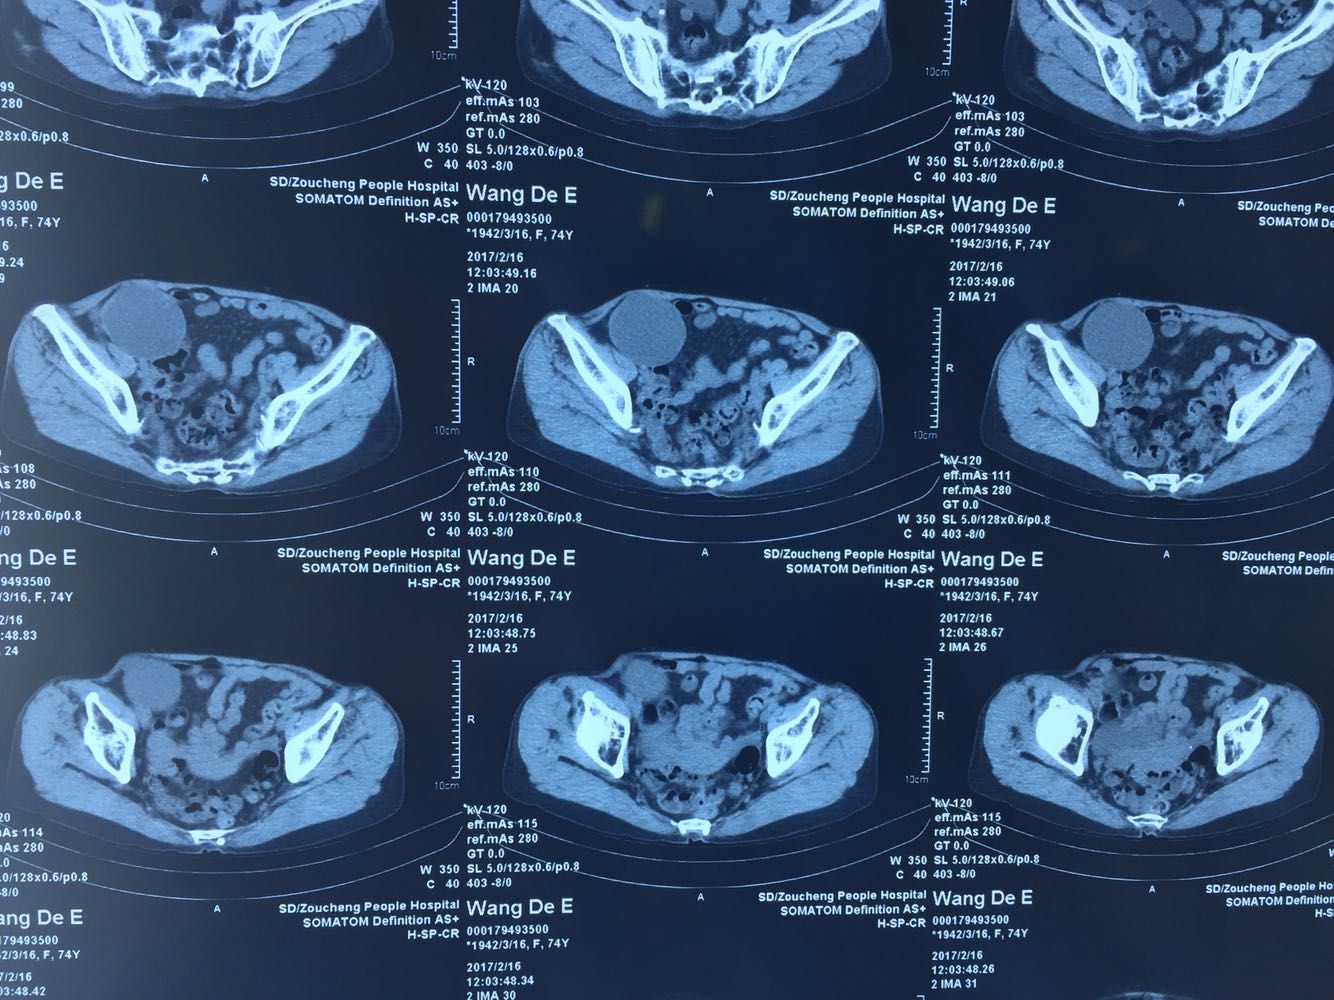

右附件区可及一大小10*8cm包块,活动度可,无压痛。 腹部CT提示右下腹多发低密度灶,考虑囊性占位。 彩超提示右腹腔内异常回声,右卵巢占位待排。